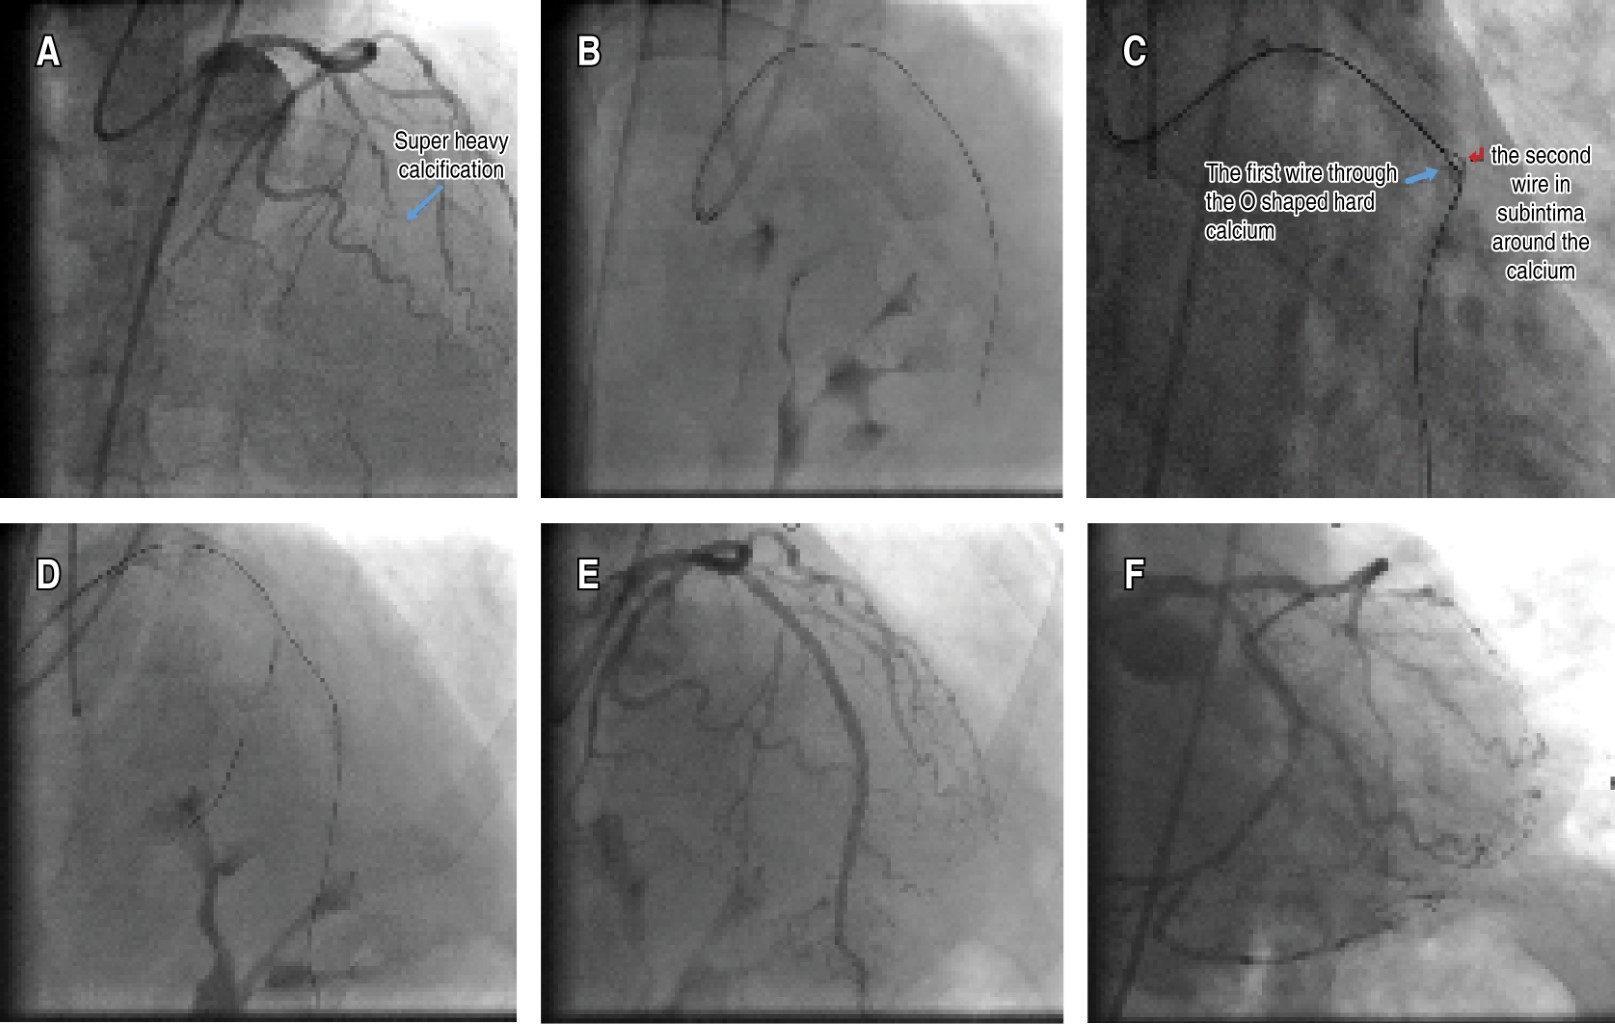

The second case was a 55-year-old male with a history of cerebrovascular disease. He was also referred to our CTO tertiary center for retry PCI of LAD CTO lesion with heavy calcification and a J-CTO score of 3 (Figure 2A). MRI revealed viability in the anterior wall and a large diagonal at the proximal cap. Again, all the steps mentioned above failed to advance the microcatheter over the wire, which could be advanced to the distal part of the vessel through the true lumen (Figure 2B). A hydrophilic wire was again knuckled and advanced around the CTO body in the subintimal space (Figure 2C). A 2 × 12 mm balloon was advanced over this wire and inflated at 6 atm. After cracking the external calcium, the microcatheter could be advanced over the wire in the true lumen. A 3 × 38 mm Drug-Eluting Stent (DES) was implanted in the LAD (Figure 2D). Then, a 2.75 × 20 mm DES was implanted in the diagonal branch using the TAP technique, and the procedure was finished successfully (Figure 2E-F).

Figure 2